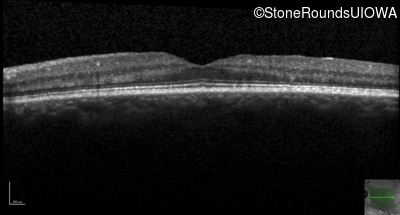

Optical Coherence Tomography - Left - 20/20 -2

Exemplar / OCT Stack